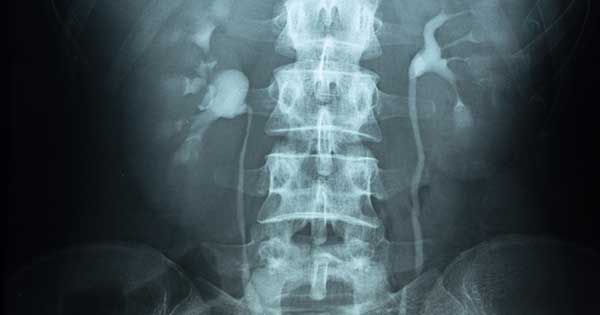

La urografía es un examen utilizado para evaluar los riñones, los uréteres y la vejiga. Existe un tipo denominado urografía excretora, también conocido como pielografía intravenosa, la cual se realiza mediante rayos X convencionales después de la administración intravenosa de material de contraste radiográfico. Dicha técnica todavía se utiliza en los niños y, ocasionalmente, en pacientes adultos más jóvenes.

La urografía por tomografía computarizada (TC) y la urografía por resonancia magnética (RM) utilizan imágenes de TC y RM, respectivamente, después de administrar el material de contraste intravenoso para obtener imágenes del tracto urinario. La urografía por TC (UTC) y la urografía por RM (URM) se usan como técnicas primarias de imagen para evaluar a los pacientes que tienen sangre en la orina (hematuria), realizar un seguimiento de los pacientes con antecedentes de cáncer del sistema colector urinario e identificar anomalías en pacientes con infecciones recurrentes del tracto urinario. Además de obtener imágenes del citado tracto, la urografía por TC y RM puede brindar información valiosa sobre otras estructuras abdominales y pélvicas, así como sobre las enfermedades que pueden afectarlas.